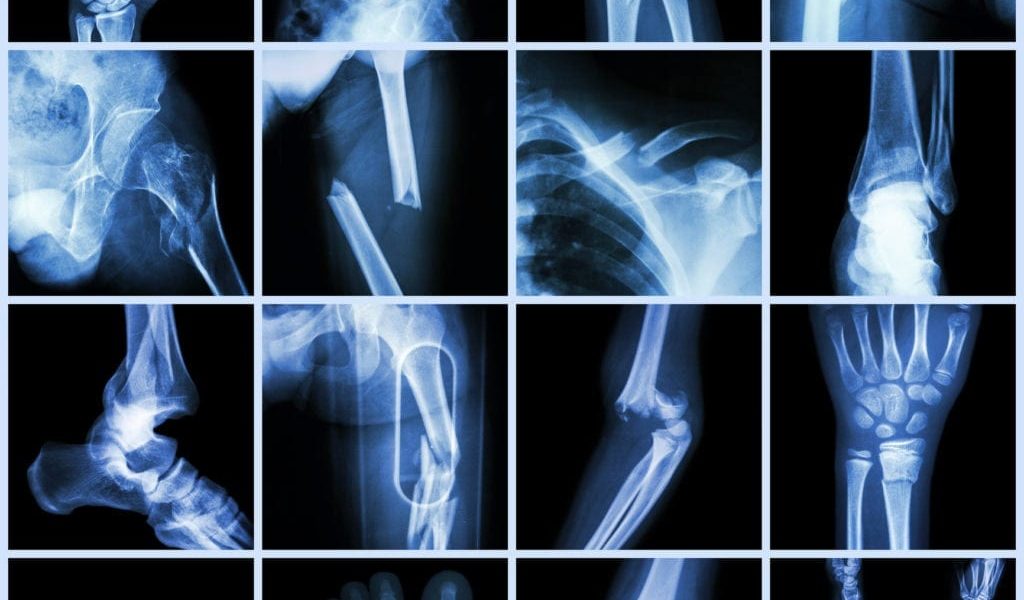

Elderly Non-Hip Fractures

Elderly Non-Hip Fractures – Hip fracture in the elderly is the most common fracture requiring hospitalization.

These fractures are frequently related to low bone mineral density and are caused by low-energy trauma.

Hip fractures are associated with increased mortality and high economic cost.

In patients over 65 years of age, fractures of the hip, thigh mid section (femoral diaphysis), and knee were associated with approximately double the mortality of the general population.

Comparison of the results regarding mortality after types of (non-hip) lower extremity fractures is difficult due to differences in study populations, ways of expressing mortality, and categorization of fracture sites. We therefore determined the mortality (compared to the general population) after all lower extremity fractures in 3,567 adults who were hospitalized for treatment of such fractures over an 9-year period.

With the exception of patients who had ankle fractures, the majority of patients treated for lower extremity fractures were over 65 years of age. 877 women and 476 men died during the study period. For elderly patients, the steepest increase in mortality was seen during the first 6 months after the fracture occurred. In younger patients, the mortality rate was constant (Figure 1).

In conclusion, we found that hip fractures in people aged 65 and over were associated with double the mortality. Notably, fractures of the femoral diaphysis and knee were associated with significantly increased mortality in this age group.